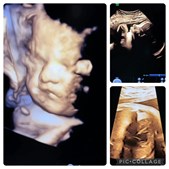

Så er der nyt fra Hjertelyd - scanningsklinik for gravide